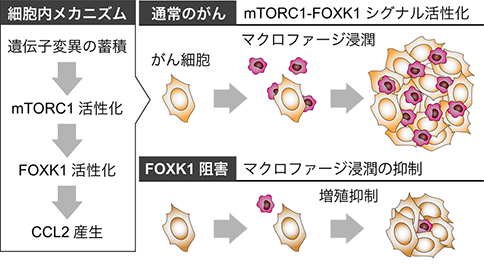

生物工学一般 腫瘍にマクロファージが浸潤する仕組みを解明

-新たながんの治療法開発に期待-九州大学国立研究開発法人日本医療研究開発機構たんぱく質リン酸化酵素であるmTORC1は様々ながんで異常に活性化されており、それががんの進行の原因になっていることは以前から知られていましたが、一方で具体的にどの...